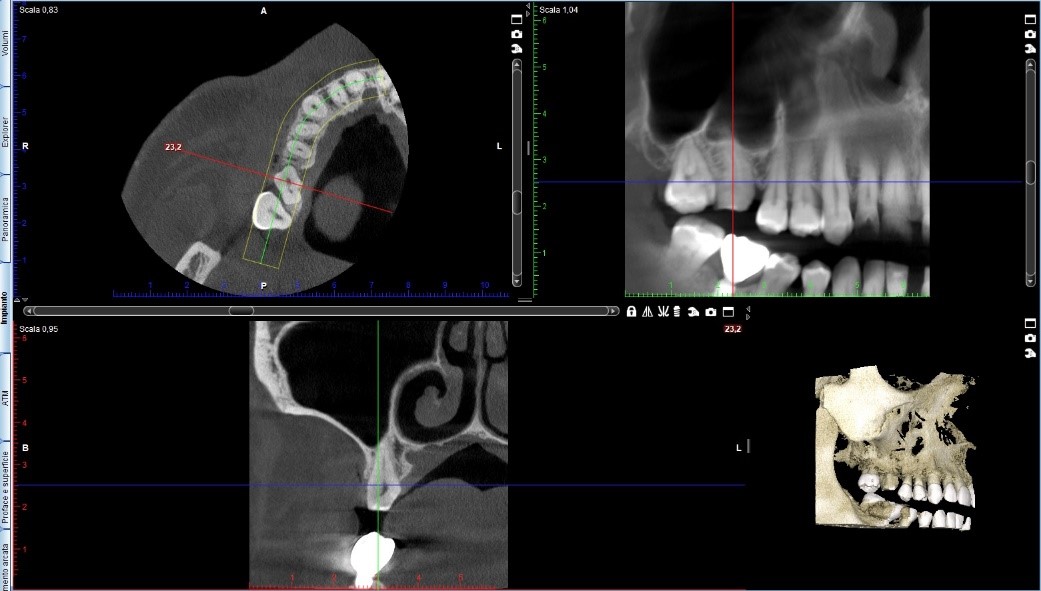

Sì perché, incredibilmente, il collega aveva fatto anche una tac. Guarda, ho fatto uno screenshot:

001

002

A parte che penso concordiamo tutti sul fatto che il dente non sia da togliere ma semplicemente da restaurare mantenendone la vitalità ma, ammesso anche che uno volesse proprio toglierlo sono sicuro che il consulente maxillofacciale del collega non avrebbe avuto la minima difficoltà nel posizionare un impianto in seguito.